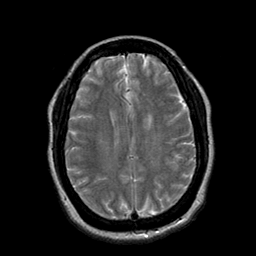

Cerebral hemorrhage, MR Study mr-t2 -- Slice #16

[Home][Help][Clinical] Slice 16